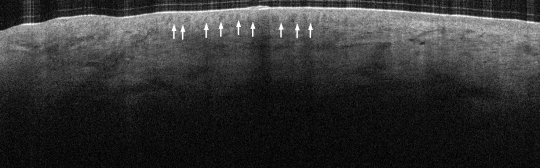

VA121: Left Mandibular Ramus, Junctional Melanocytic Nevus, Dysplastic

- Arrows indicate rete elongations